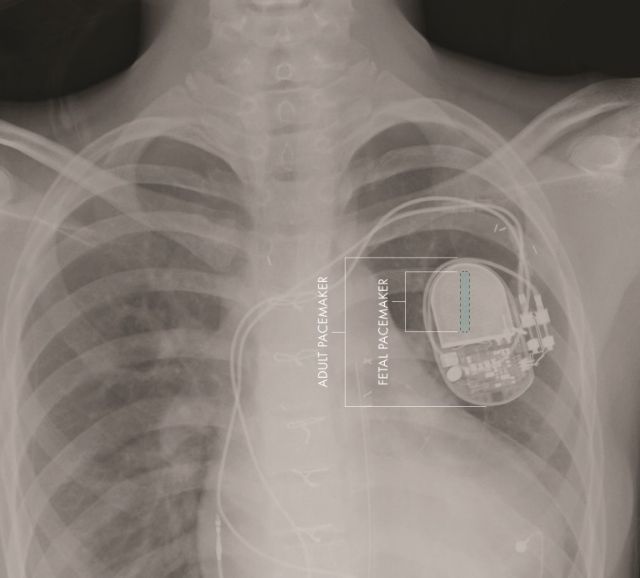

Ένας πειραματικός βηματοδότης που αναπτύχθηκε σε αμερικανικό νοσοκομείο είναι αρκετά μικρός ώστε να εμφυτευθεί στο αναπτυσσόμενο έμβρυο.

Μέχρι σήμερα, οι μόνοι βηματοδότες που μπορούσαν να χρησιμοποιηθούν σε τέτοιες περιπτώσεις ήταν οι σχετικά ογκώδεις βηματοδότες για ενήλικες, οι οποίοι όμως δεν χωρούν στο σώμα του αναπτυσσόμενου εμβρύου. Για τον λόγο αυτό, ο βηματοδότης παρέμενε έξω από το σώμα της μητέρας, και μόνο τα ηλεκτρόδιά του έφταναν μέχρι την καρδιά του εμβρύου.

Ο νέος βηματοδότης, ένας μεταλλικός κύλινδρος μήκους μερικών εκατοστών, προορίζεται για έμβρυα που πάσχουν από πλήρη καρδιακό αποκλεισμό, μια πάθηση που αφορά το ηλεκτρικό σύστημα της καρδιάς.